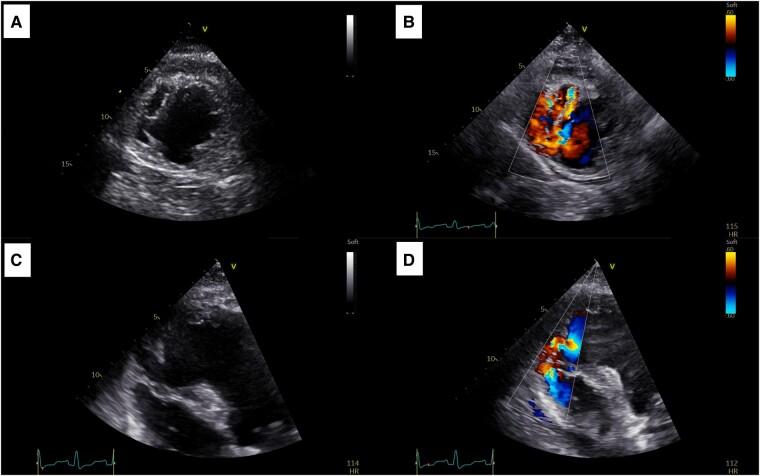

CASE SUMMARY

We describe a TTS case presented with cardiogenic shock due to ventricular septal rupture (VSR). Successful treatment involved mechanical circulatory support followed by VSR surgical closure.

我们描述了一例因室间隔破裂(VSR)导致心源性休克的TTS病例。成功的治疗包括机械循环支持,随后进行VSR手术闭合。